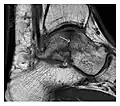

Figure 7: Fatigue fracture of the talus in a 25-year-old male basketball player with right hind foot and ankle pain, without history of trauma, and a normal initial radiograph (not shown). (a) One-month followup lateral radiograph shows normal appearance. (b) Sagittal T1-weighted MRI shows an irregular fracture line (arrow) within an ill-defined area of hypointensity corresponding to bone marrow edema.[1]

Figure 8: Proximal diaphyseal fatigue fracture of the tibia in a 20-year-old man with a history of regular jogging. (a) Lateral radiograph shows no obvious fracture lines but a subtle localized medial tibial cortex periosteal reaction (arrows). (b) Sagittal reformatted CT image acquired 1-month after the radiograph shows a linear hypoattenuation in the tibial cortex (arrowhead), as well as obvious periosteal thickening (arrows). (c) Sagittal T2-weighted fat-saturated image acquired the same day shows an area of hyperintensity spreading over the proximal tibia (arrows), which is consistent with the presence of proximal tibial fracture.[1]

Figure 9: Proximal metaphyseal fatigue fracture of the tibia in a 27-year-old recent male military recruit. (a) Anteroposterior radiograph is within normal limits. (b) Coronal T1-weighted MR image shows a marked linear hypoattenuation along the medial tibial metaphysis (arrow) surrounded by diffuse hypointensity in keeping with posttraumatic edema.[1]

Figure 10: Calcaneal fatigue fracture in a 30-year-old male runner. Radiographs were normal (not shown). (a) Sagittal T1-weighted and (b) short tau inversion recovery images show a linear hypointensity (arrows) of calcaneal tuberosity within diffuse bone marrow edema, which appears as an ill-defined area of hyperintensity on a fluid sensitive pulse sequence (arrowheads).[1]